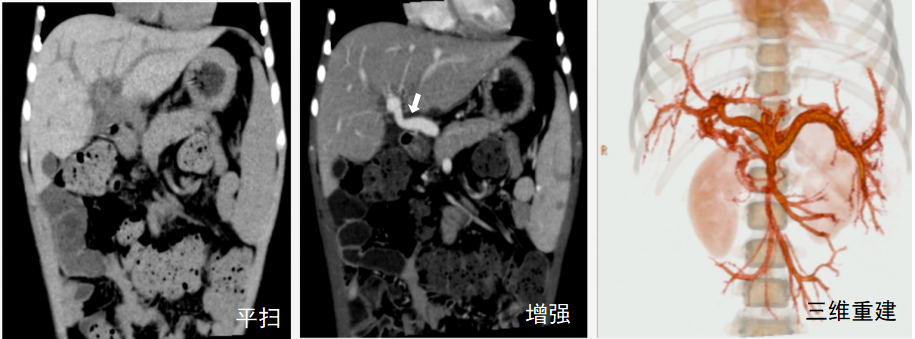

如下图,通过增强扫描,医生能清晰判断肿瘤与周围重要血管的关系,这对于制定安全的手术方案至关重要。

CT增强扫描示肝巨大占位性病变与重要血管(箭头)的关系

CT增强扫描应用于门脉高压Rex术后吻合血管情况评估(白箭:吻合血管)